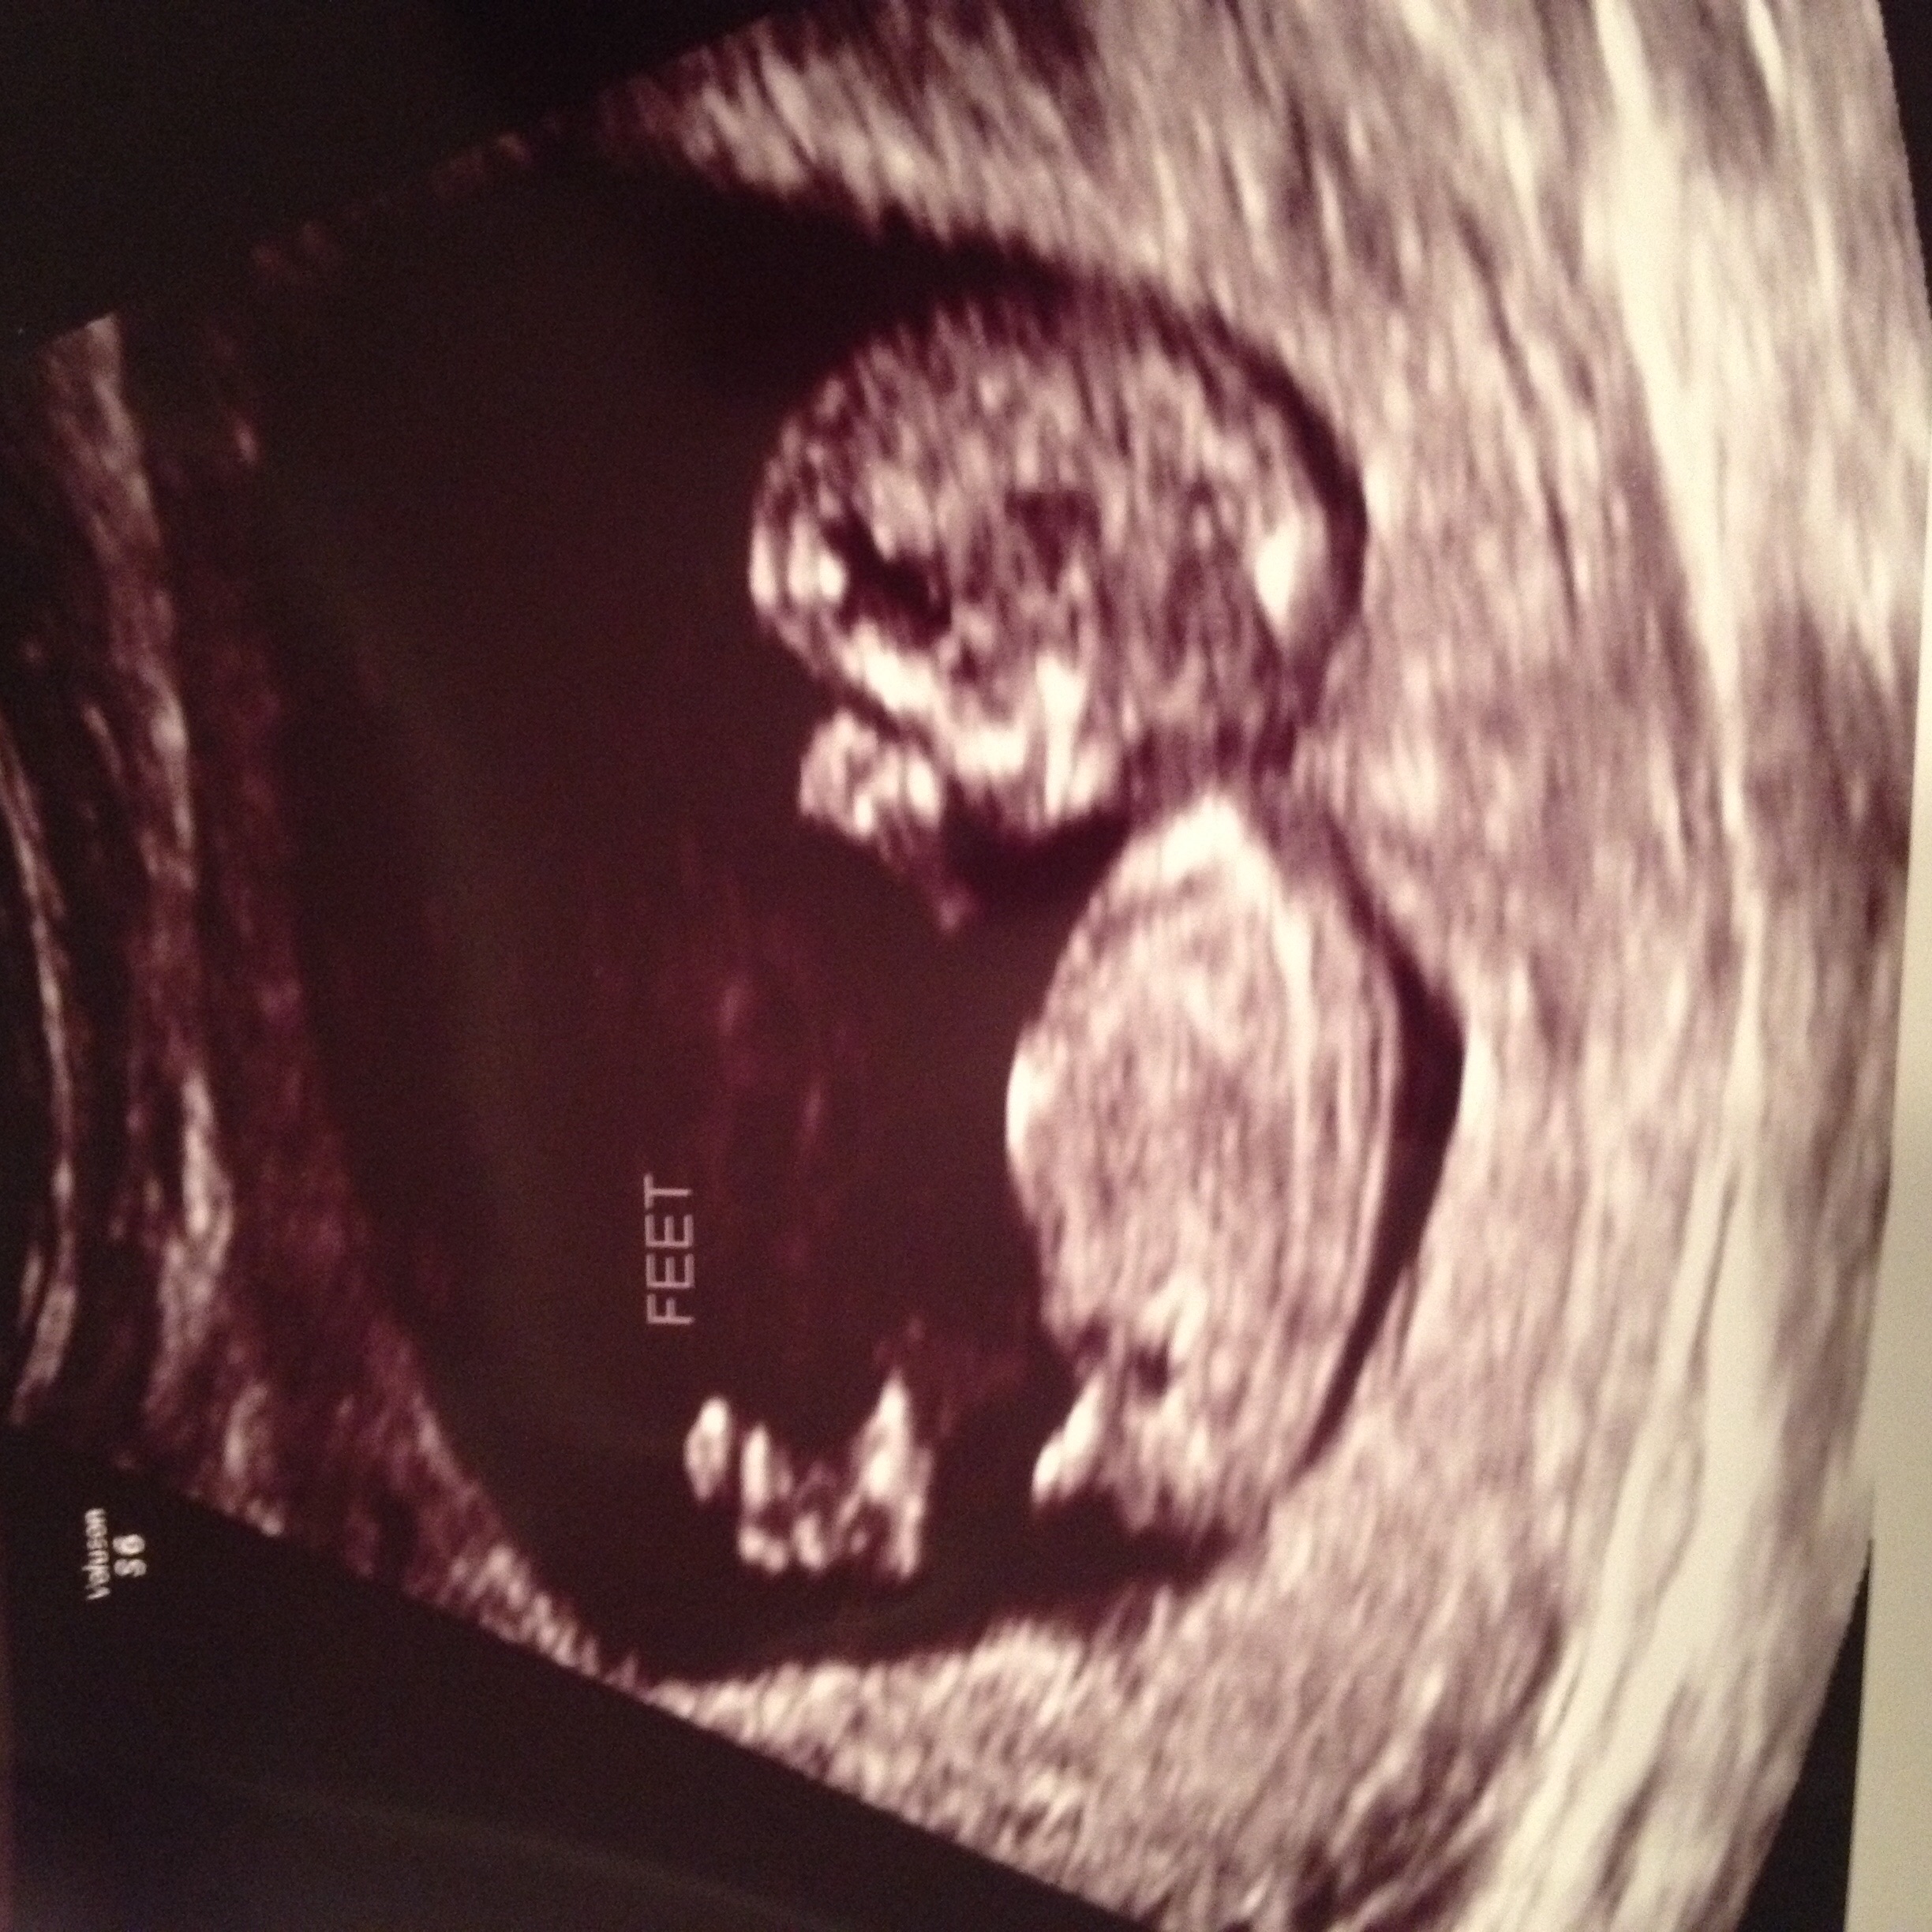

Gotta be a boy right? This was from 12w4d, and that little nub definitely looks like a wiener. What do you think, did your boys look like that at 12 weeks?

• Based on "nub theory", they guessed boy but obviously won't be confirmed for another month

• Yes, very boyish. You are actually looking at the Nub, which depending on angle, can offer a sex insight at 12-13 weeks. Forked and/or flat with a downward trend indicated girl. Bulgy and/or upward trend indicates boy.

• Yes nub looks boy to me. My guess is for blue